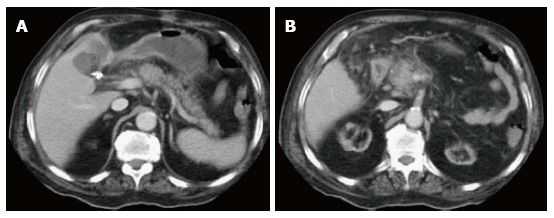

Изображение 3. 30-летняя женщина получила травму живота во время ДТП. Изображение МСКТ показывает линейный гиподенсный участок перпендикулярно длиннику поджелудочной железы в области хвоста (белая стрелка), что указывает на разрыв хвоста III степени.

Изображение 4. 55-летний мужчина после удара бейсбольной битой по животу. На МСКТ-снимке (А) обнаружена большая рваная рана головки поджелудочной железы (стрелка), затрагивающая более 50 % толщины паренхимы и указывающая на высокую вероятность повреждения протока.

На магнитно-резонансной холангиопанкреатографии (В) у того же пациента подтверждается повреждение протока (стрелка).

Изображение 5. Разрыв поджелудочной железы IV степени у 41-летнего мужчины, пострадавшего в результате ДТП. На МСКТ (А) показан линейный разрыв (стрелка) в головке поджелудочной железы справа от верхней брыжеечной вены.

На МРТ (В) изображение того же пациента демонстрирует разрыв в головке поджелудочной железы (стрелка).